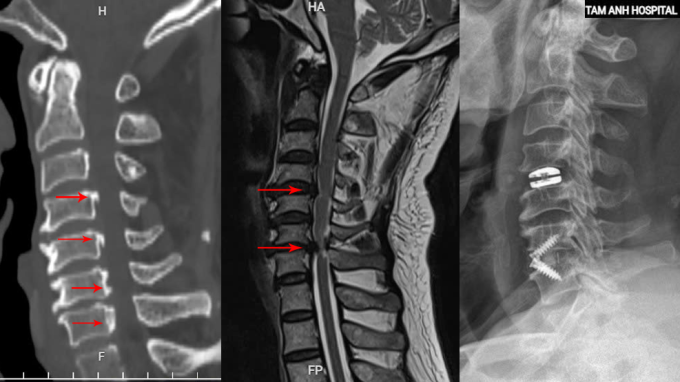

Chụp cắt lớp vi tính CT tại Bệnh viện Đa khoa Tâm Anh Hà Nội phát hiện bệnh nhân vôi hóa nhiều đoạn dây chằng dọc sau. ThS.BS Tạ Ngọc Hà, khoa Chấn thương Chỉnh hình, giải thích lớp dây chằng này có nhiệm vụ giữ vững cột sống, bị canxi hóa và dày lên, làm hẹp ống sống từ đốt sống cổ C3 đến C7. Chụp cộng hưởng từ MRI cho thấy đĩa đệm C4-5 thoát vị, C6-7 thoát vị nặng, chèn ép tủy cổ nghiêm trọng.

Phương án phẫu thuật tối ưu, an toàn cho người bệnh là mổ lối trước, bộc lộ mặt trước thân đốt sống, thay đĩa đệm nhân tạo C4-5, cố định đốt sống C6-7, theo bác sĩ Hà. Cách này giúp bệnh nhân bảo tồn vận động cổ sau mổ.

Trong 4 tiếng, bác sĩ Hà cùng êkíp dùng kính vi phẫu bóc tách, giải phóng vùng tủy bị chèn ép. Khối thoát vị C4-5 được lấy ra ngoài, đặt đĩa đệm nhân tạo thay thế. Tổn thương đốt sống C6-7 nặng hơn được bác sĩ Hà lấy bỏ đĩa đệm và thoát vị chèn ép, giải phóng thần kinh rồi ghép xương nhân tạo và cố định lại bằng miếng ghép đĩa đệm có nẹp vít để tạo độ vững cho toàn bộ cột sống cổ.